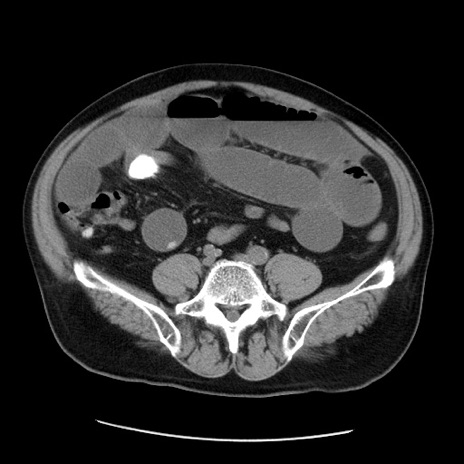

症例20(横断像)

【症例】 60歳代男性

【主訴】 腹部膨満、嘔吐

【現病歴】5日前頃より倦怠感を認め食事量減少し4日前の朝嘔吐、食事摂取困難となった。 3日前近医受診し点滴施行され整腸剤などを処方された。 当日他院を受診し、腹部膨満著明、炎症反応の上昇(CRP10.8、WBC11200)あり、紹介受診となる。

【身体所見】 意識JCS1 受け答えがはっきりしないBP 111/57mHg、 P 67bpm、、BT35.2°C、SpO2 97%(RA)、 腹部:膨隆、打診で鼓音あり、全体的に圧痛有り、腸蠕動音(-)、反跳痛ははっきりせず。

【データ】WBC 11400、CRP 14.20